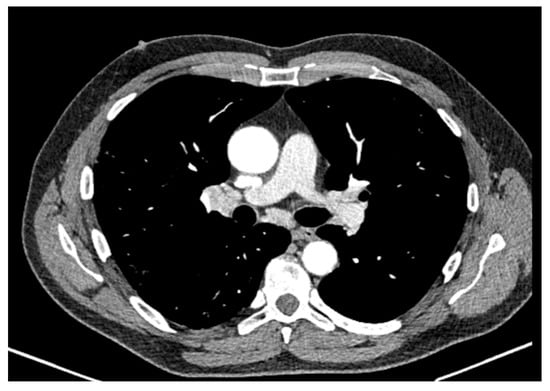

2. Case Report